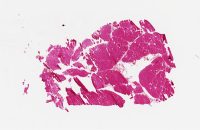

CANP2008-11.svs

22000 x 24665

@ 20X